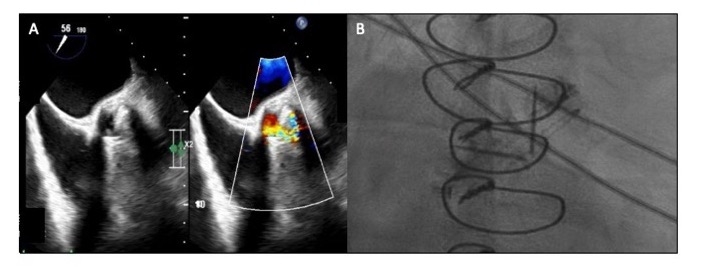

He was found to have SCAI-C cardiogenic shock, with exam notable for III/VI systolic crescendo-decrescendo and IV/IV decrescendo early diastolic murmurs, and absent mechanical click. Labs were notable for absolute eosinophils of 11.5 K/cu mm. On TTE, valve disks were poorly visualized. The mean gradient was 59mmHg and there was severe aortic insufficiency with preserved ventricular function. Due to concern for valvular obstruction, TEE was performed, revealing a well-seated valve with severe valvular regurgitation originating posteriorly and a reduction in systolic excursion of the disks. Valve fluoroscopy showed minimal movement of both discs suggesting thrombosis.

The patient was deemed high risk for surgical intervention and therefore received systemic thrombolysis with alteplase 25mg over 6h x2. Repeat TTE showed mean gradient 29mmHg, and mild-moderate aortic insufficiency. Eosinophilia peaked at 16.7 K/cu mm and normalized with high-dose prednisone. Eosinophilia workup is ongoing.